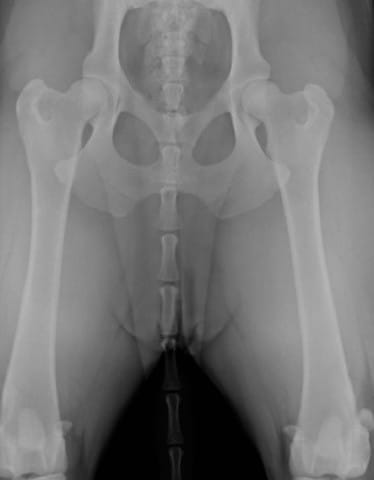

Je dois adopter une petite chienne cocker dans 2 mois. J’ai fait les démarches de réservation en envoyant un chèque qui s’avère être des Arrhes. Aujourd’hui une information supplémentaire s’est ajoutée sur le site de l’élevage concernant la mère des chiots, elle a une dysplasie de type C donc légère. Le père lui est de type B donc presque normal. C’est une maladie qui est héréditaire, par conséquent les chiots ont 50% de chance de présenter cette maladie.